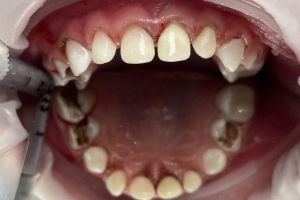

Семейная областная стоматология "Кидди Дентал" - это команда компетентных врачей, каждый из которых знает и любит свое дело. Опыт наших врачей, использование современного оборудования и надежных материалов позволят проводить лечение любой сложности.